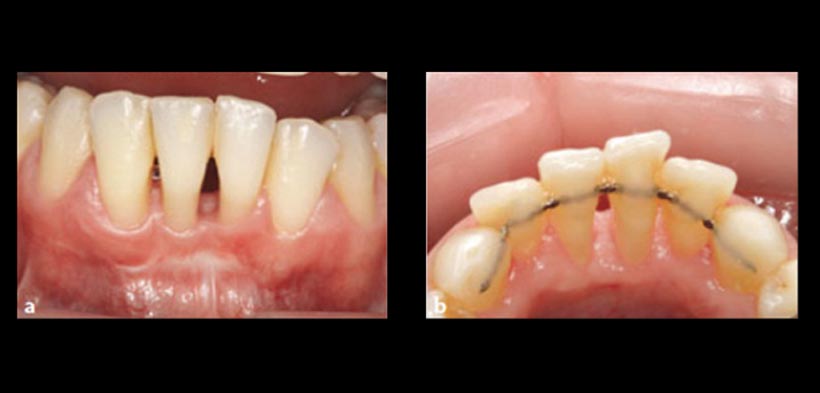

Fig. 2. Fotografías que pertenecen al paciente anterior. (A) vista vestibular (B) vista lingual. 2 años post tratamiento, muestra una encía saludable.